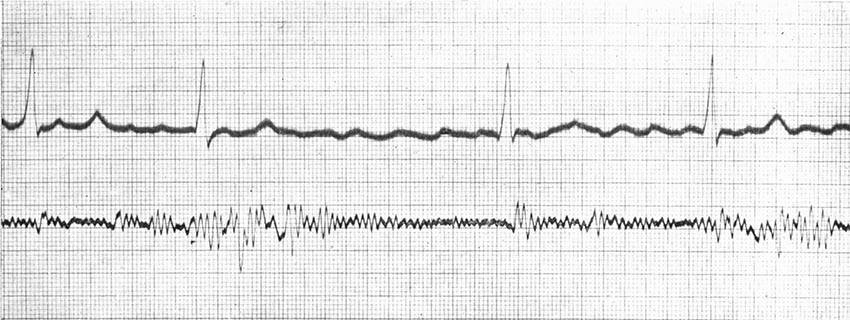

| Continuous Moving-pictures of Heart-beats of an Excited Person | 137 |

| Continuous Cinematography—Palpitations of a Rabbit's Heart | 142 |